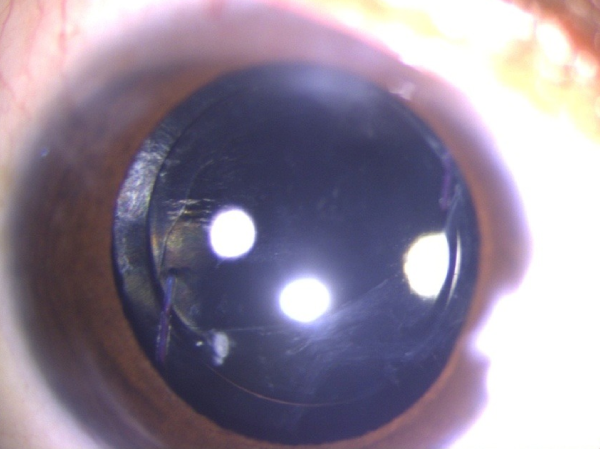

Posterior polar cataract post operative result after surgery in Kerala eye hospital

Post-Operative